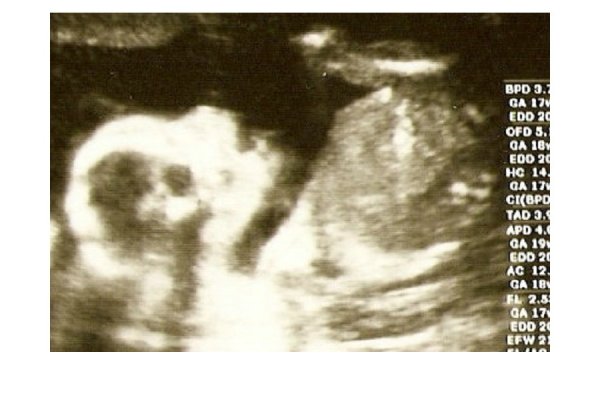

Voltam ma UH-on. Minden rendben van vele, nagzon aranyosan rugdosodt. Es megmutatott mindent, igy lehetett latni, hogy kislany. Bar azt mondta a doki, hogz ne vegyem azert 100%ra.

Ime egy kép róla:

Kép